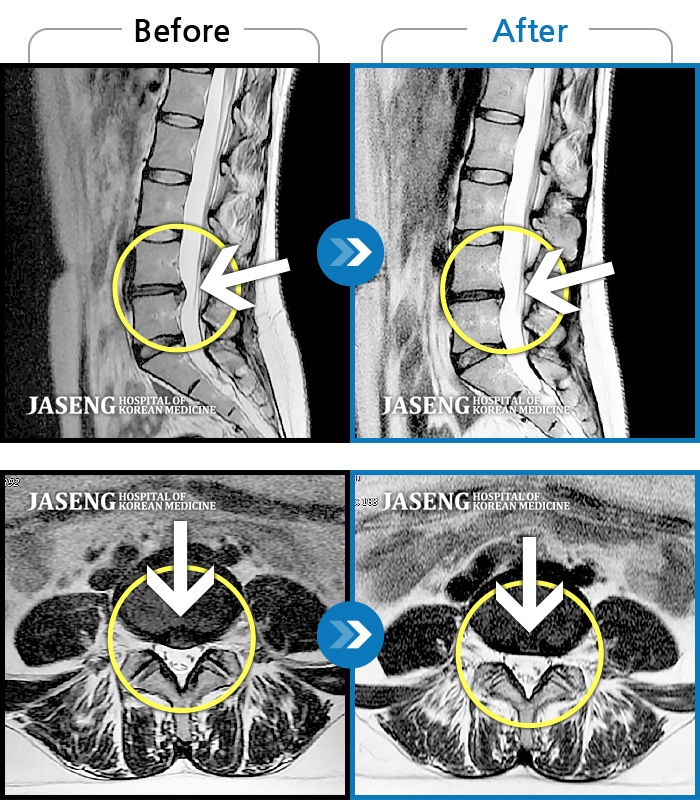

MRI 치료사례

허리 통증이 심해서 의자에 앉기도 힘들었어요